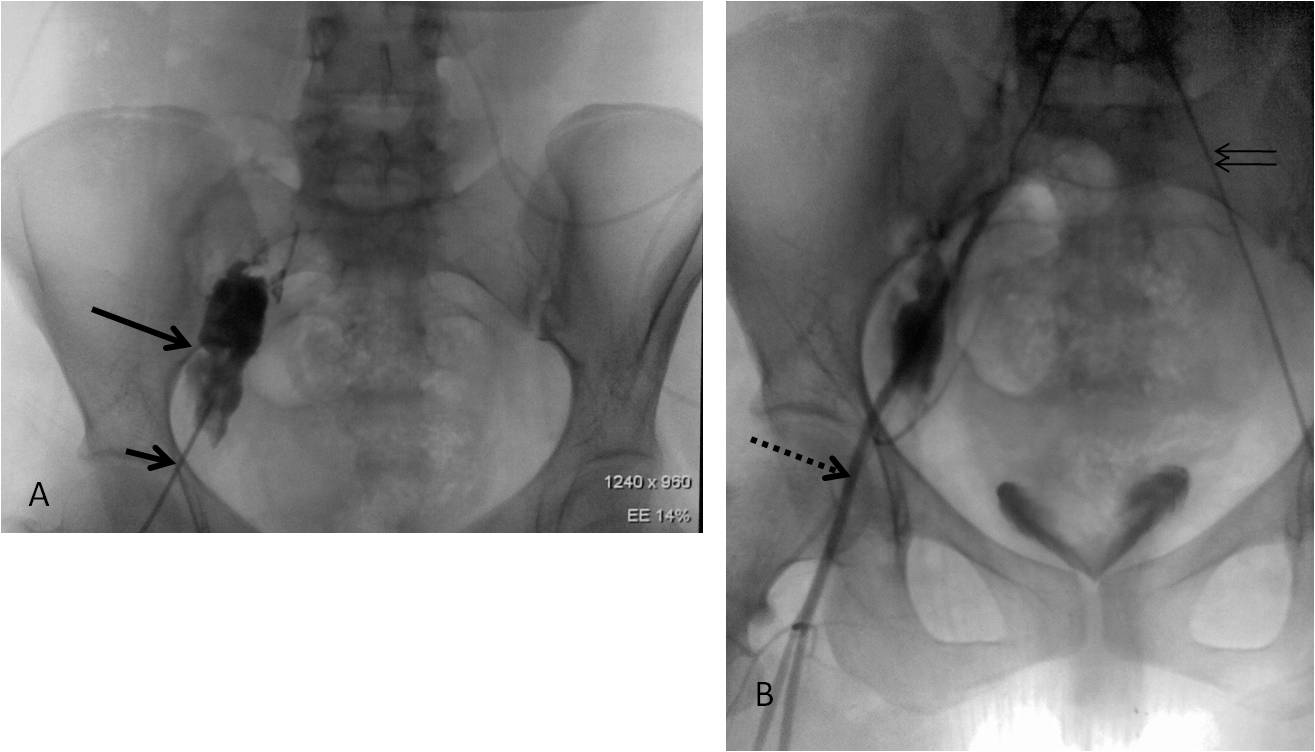

Science Of Neurointervention Inguinal Canal And Retroperitoneal Hematoma During Femoral Puncture